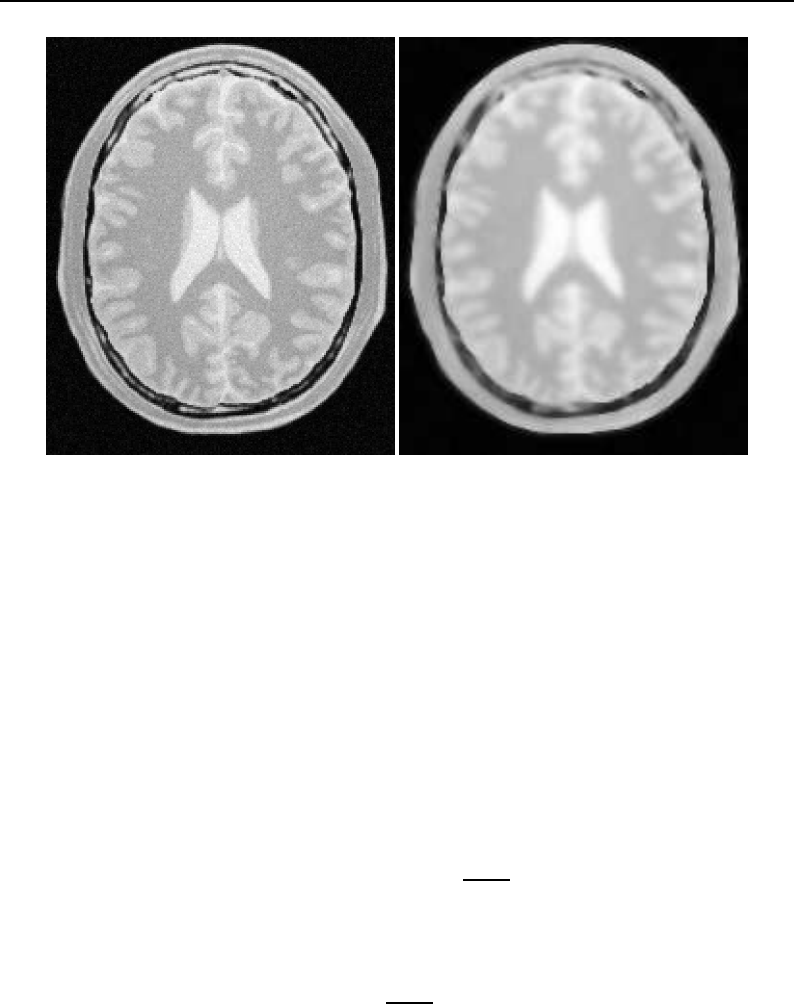

The National Library of Medicine Insight Segmentation and Registration Toolkit, shortened as the

Insight Toolkit (ITK), is an open-source software toolkit for performing registration and segmenta-

tion. Segmentation is the process of identifying and classifying data found in a digitally sampled

representation. Typically the sampled representation is an image acquired from such medical instru-

mentation as CT or MRI scanners. Registration is the task of aligning or developing correspondences

between data. For example, in the medical environment, a CT scan may be aligned with a MRI scan

in order to combine the information contained in both.